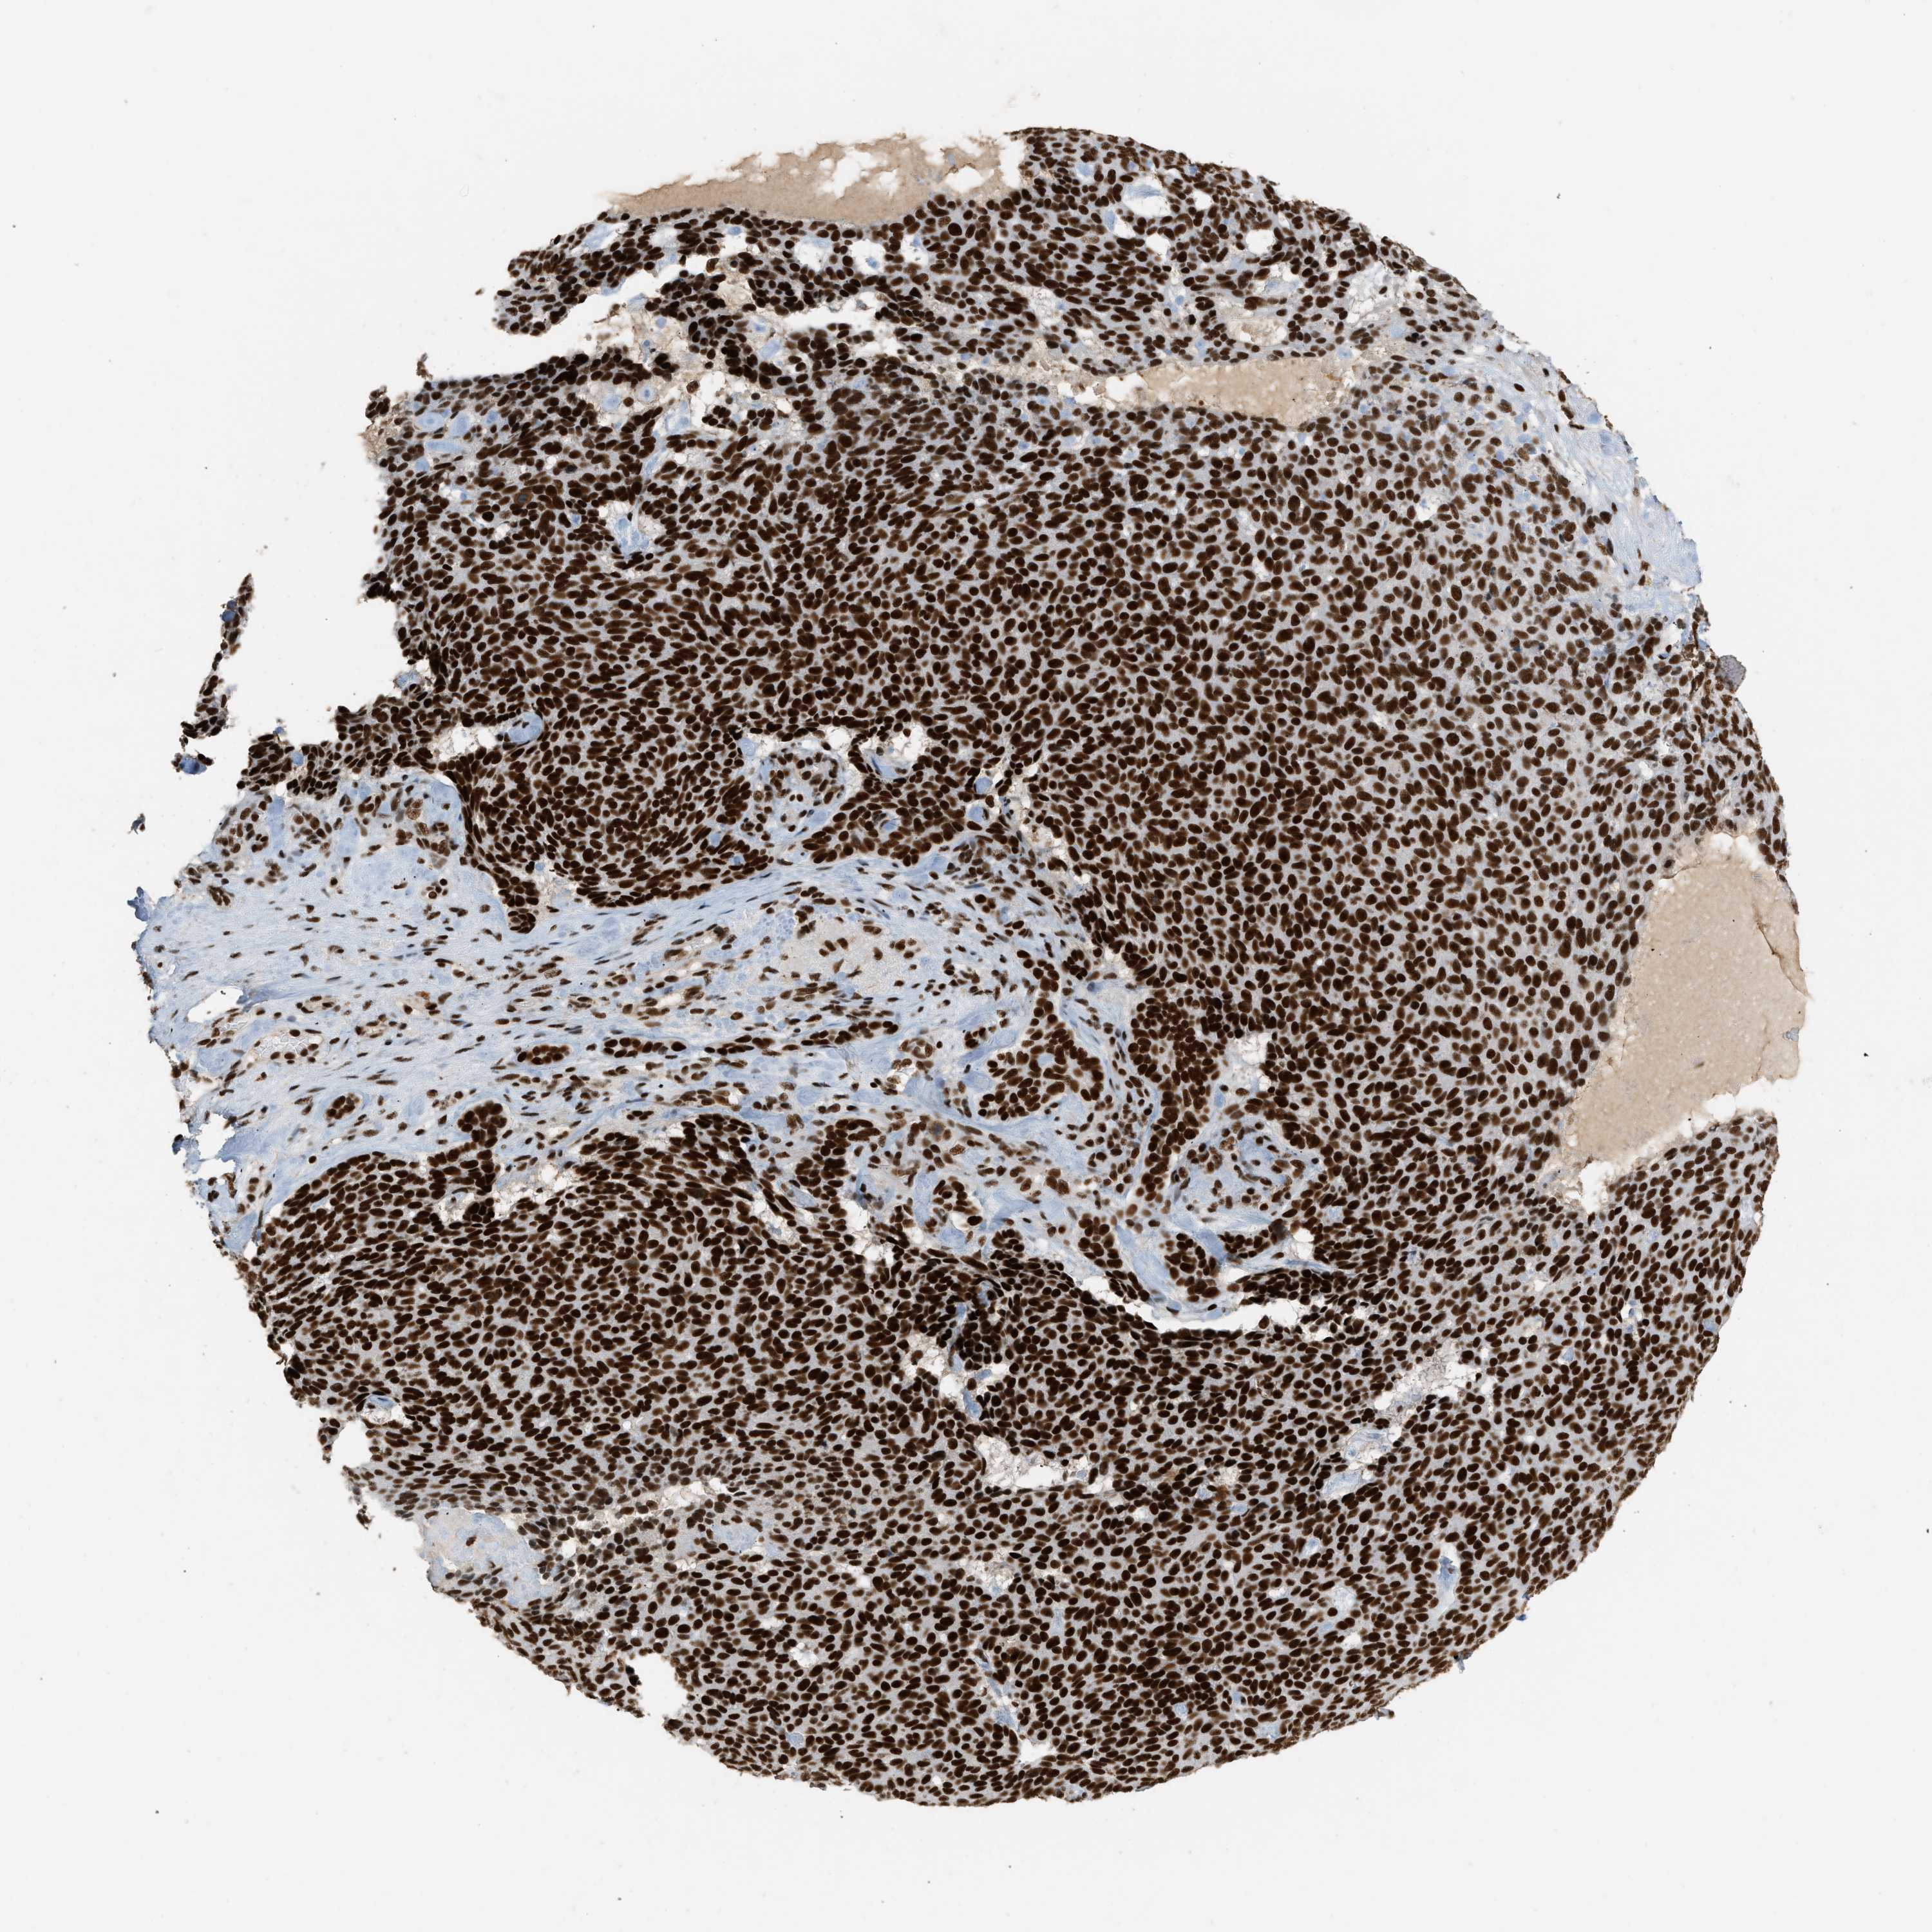

SKIN CANCER - Protein expressioni

A mouse-over function shows sample information and annotation data. Click on an image to view it in a full screen mode. Samples can be filtered based on level of antibody staining by selecting one or several of the following categories: high, medium, low and not detected. The assay and annotation is described here.

Each image is clickable and will lead to virtual microscopy that enables deeper exploration of all samples and also displays staining intensity scores, fraction scores and subcellular localization as well as patient and tissue information for each sample.

Antibody HPA019127

Staining

High

Medium

Low

Not detected

Intensity

Strong

Moderate

Weak

Negative

Quantity

>75%

75%-25%

<25%

None

Location

Nuclear

Cytoplasmic/membranous

Cytoplasmic/membranous,nuclear

Basal cell carcinoma